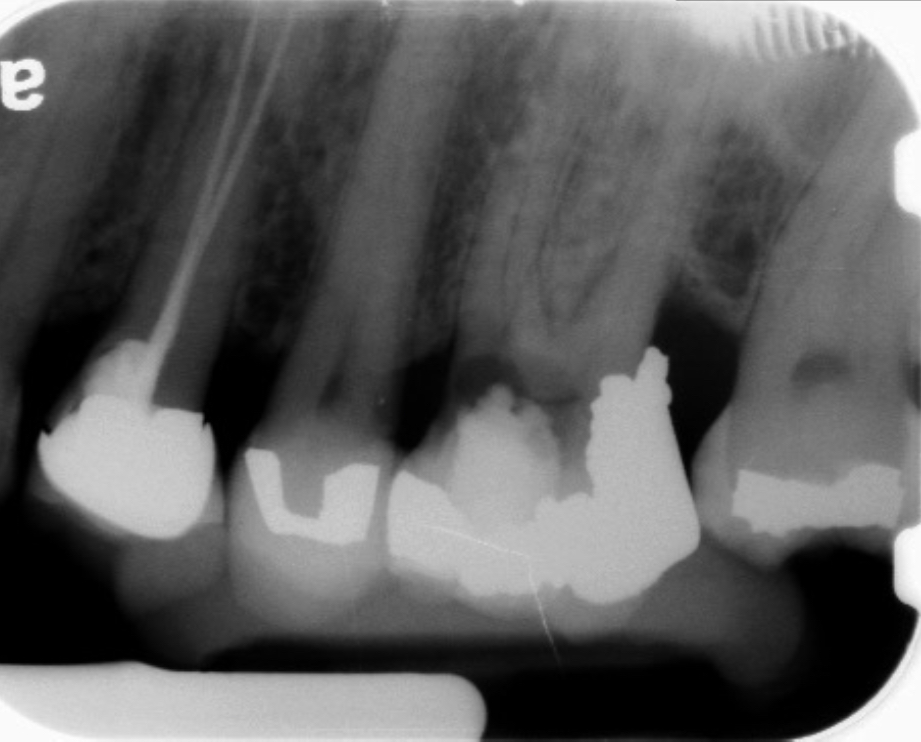

Fig 9 Preoperative radiographs showing mesial perforation.

Figure 9

Fig 10. Preoperative radiographs showing mesial perforation.

Figure 10

Fig 11. MTA perforation repair done, and calcium hydroxide medication placed in the canals.

Figure 11

Fig 13. 2-year follow-up radiographs showing the positive outcome.

Figure 13

Fig 14. 2-year follow-up radiographs showing the positive outcome.

Figure 14